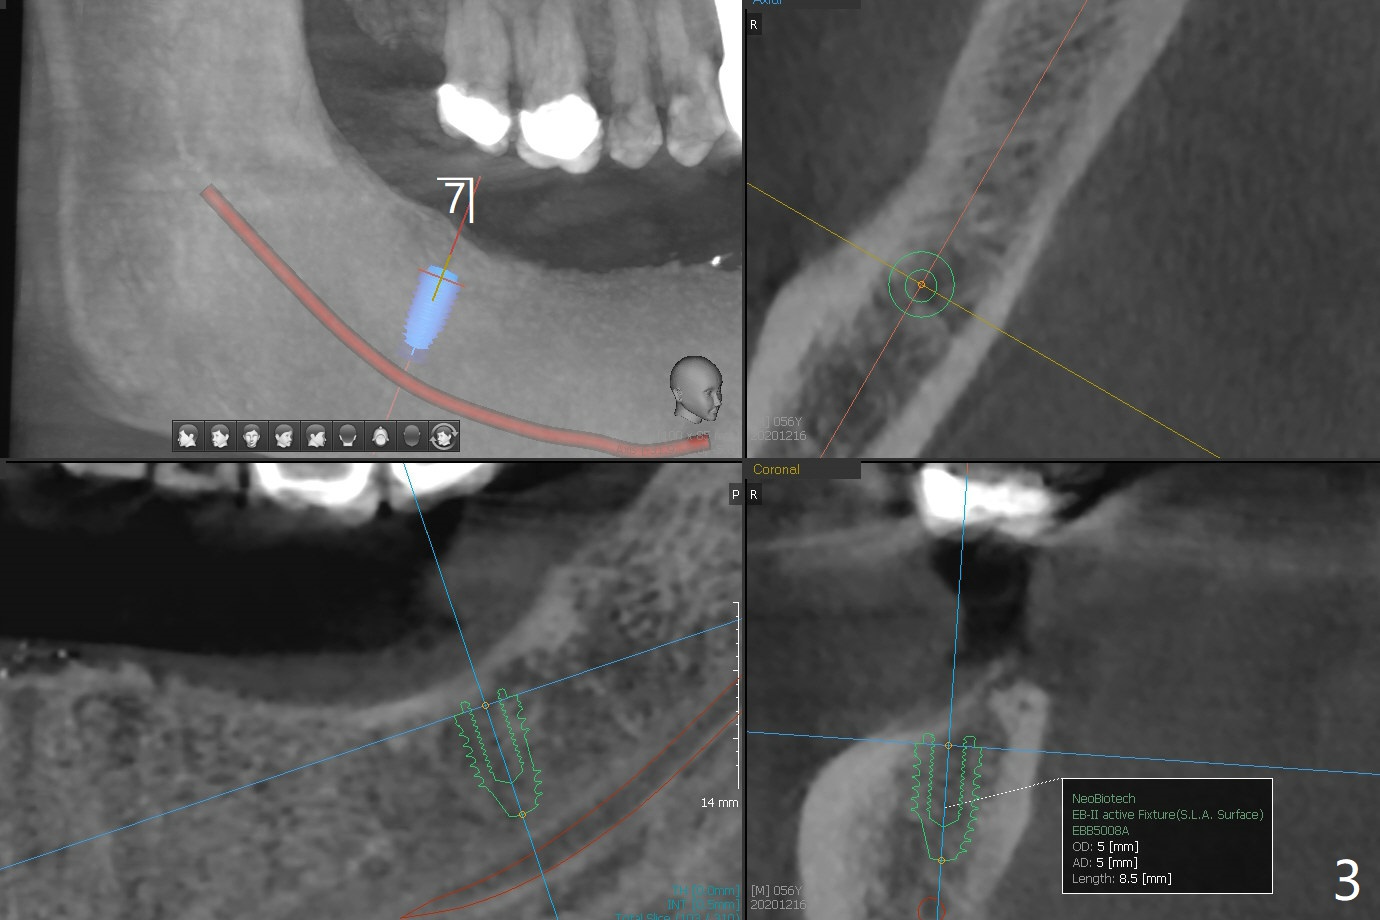

56岁男下颌可弯曲局部义齿(Valplast)靠托牙胶水固定,造成左下2远中颈部龋齿,后者修复后(图一),考虑在下7种植(图二,三),放置球帽基台固定义齿,改善口腔菌群。